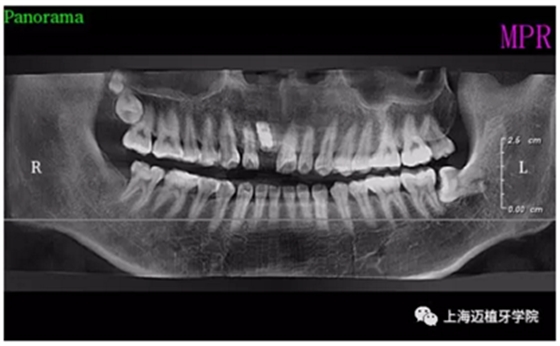

主訴:前門外傷牙根折要求修復(fù)?現(xiàn)病史:前門牙外傷,劈裂至根部,無法固定及其他修復(fù),要求種植?檢查:11牙冠2/3缺損,唇腭向劈裂,唇部紅腫。 CT示根折, 骨寬度9.47mm,距鼻底12.34mm,Ⅲ類骨。 口腔衛(wèi)生一般

術(shù)前全景片

術(shù)后全景片